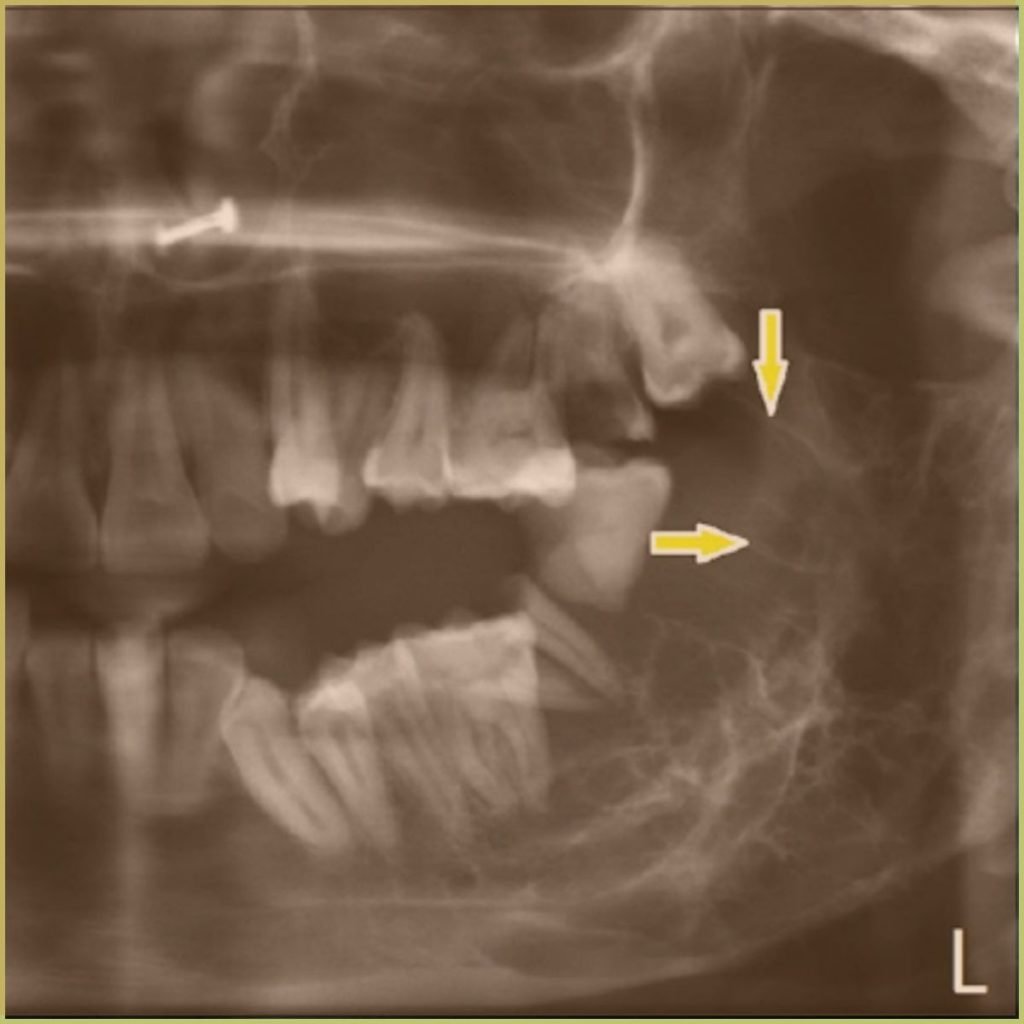

ODONTOGENIC MYXOMA

Odontogenic Myxoma is a rare but aggressive benign odontogenic neoplasm that probably arises from the mesenchymal portion of the tooth germ. It is the third most frequent odontogenic tumor after odontoma and ameloblastoma. The common clinical presentation includes:

- Well-defined unilocular or multilocular radiolucency that ranges from a small “honeycomb” appearance to a large “soap bubble” shape.

- Commonly associated with an unerupted tooth.

- Cortical thinning may be present but perforation is uncommon.

- Usually asymptomatic.

- May cause slow painless jaw expansion.